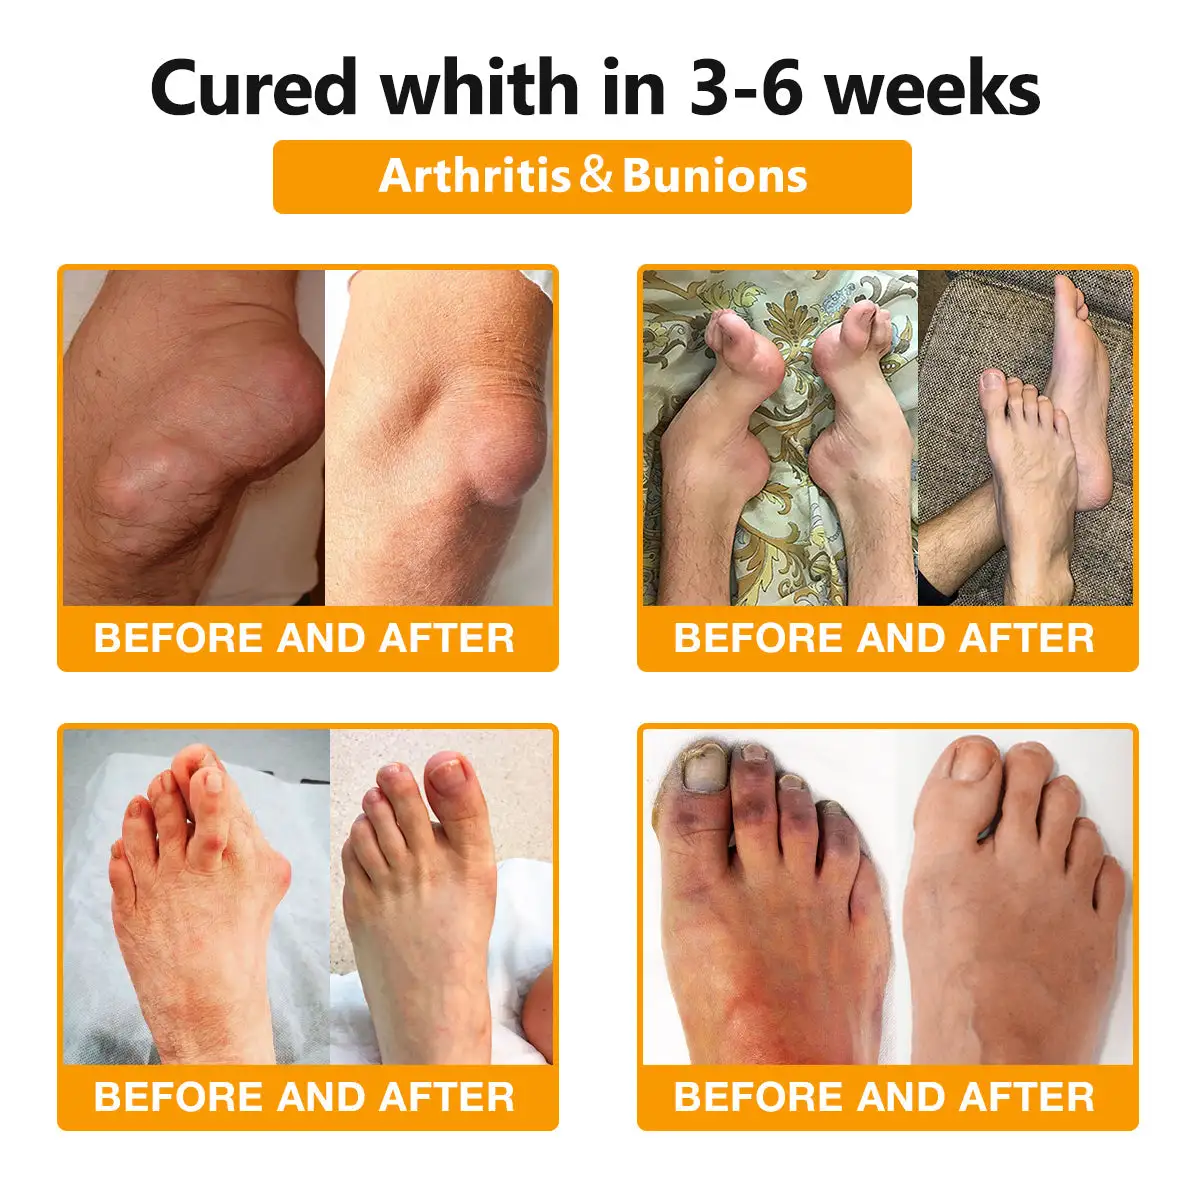

The ArthroFree™ Bee Venom Pain-Relief Bone Healing Cream is celebrated for its efficacy in addressing a wide array of orthopedic conditions. These include osteoarthritis, rheumatoid arthritis, bursitis, tendinitis, osteoporosis, gout, carpal tunnel syndrome, ligament sprains and strains, bunion deformities, and tennis elbow.